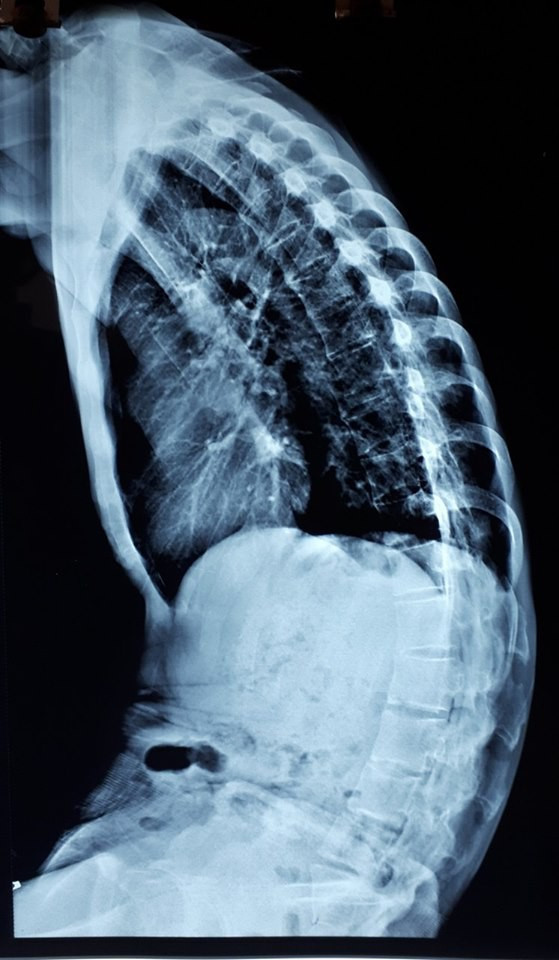

| Hình ảnh cho thấy bệnh nhân bị biến dạng gù cột sống nặng. |

Biến dạng gù nặng cột sống khiến bệnh nhân gập cả thân mình, đi khuỳnh chân, mắt không nhìn được xa (chỉ nhìn thẳng xuống đất) gây khó khăn lớn cho vận động. Ngoài ảnh hưởng đến chức năng vận động, tình trạng này còn khiến hệ hô hấp, tiêu hóa của bệnh nhân gặp khó khăn do cột sống gù gập chèn ép lồng ngực và ổ bụng. Bệnh nhân thường bị đầy bụng, khó tiêu, đau tức ngực, thi thoảng khó thở.

Bệnh nhân có mức độ gù lớn không thể nhìn thẳng được. Để nhìn đường khi đi bộ, người bệnh phải ngửa cổ, gấp khớp háng và khớp gối. Người bệnh tự ti về dáng vẻ bề ngoài của mình. Phẫu thuật nhằm mục đích cải thiện tầm nhìn thẳng, giúp người bệnh dễ dàng khi đi lại và tự tin hơn.